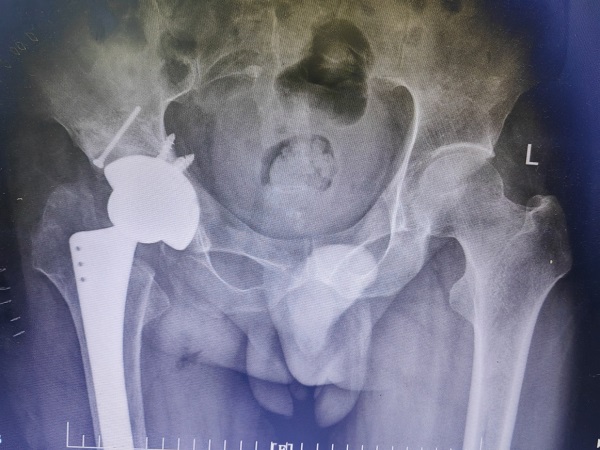

為了順利手術,在完善髖臼骨缺損的墊塊、異體股骨頭等結構性植骨材料、陶對陶全髖關節(jié)假體的準備后,郭永良主任醫(yī)師主刀,王爭剛主任醫(yī)師等輔助,歷時2小時,手術順利完成。術后患者雙下肢等長,無神經、血管損傷。目前術后三周,患者可扶拐逐漸負重下地行走,相信經過一段時間的康復和鍛煉,李師傅可再次回歸社會,恢復正常的生活和工作。